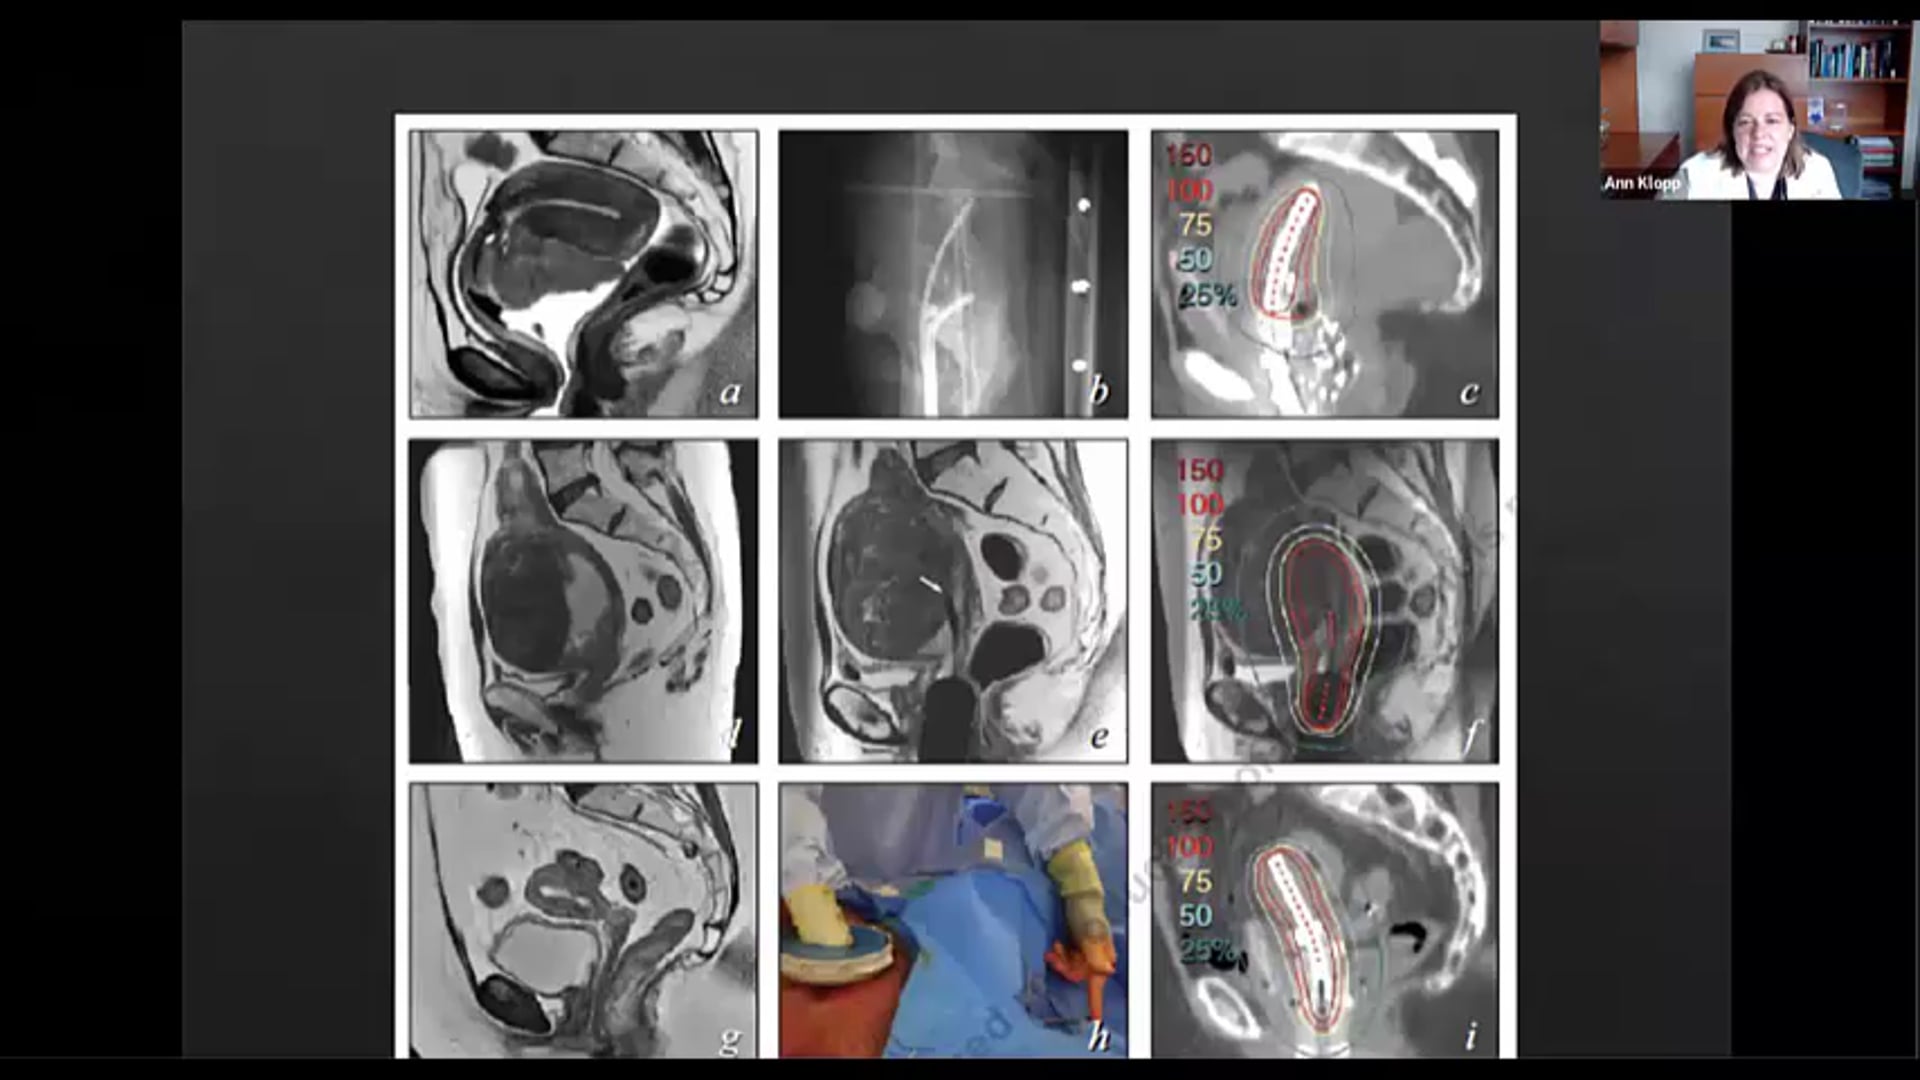

11/12/20 - Dr. Ann Klopp - Radiation Oncology - GYN Brachytherapy

cervical cancer brachytherapy, defining a volumetric target, dose constraints, applicator design, external beam, standard fractionation,